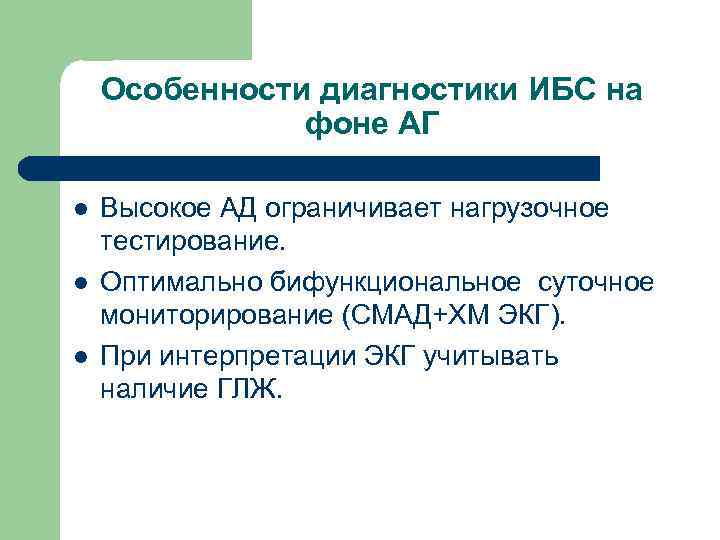

Особенности диагностики ИБС на фоне АГ l l l Высокое АД ограничивает нагрузочное тестирование. Оптимально бифункциональное суточное мониторирование (СМАД+ХМ ЭКГ). При интерпретации ЭКГ учитывать наличие ГЛЖ.